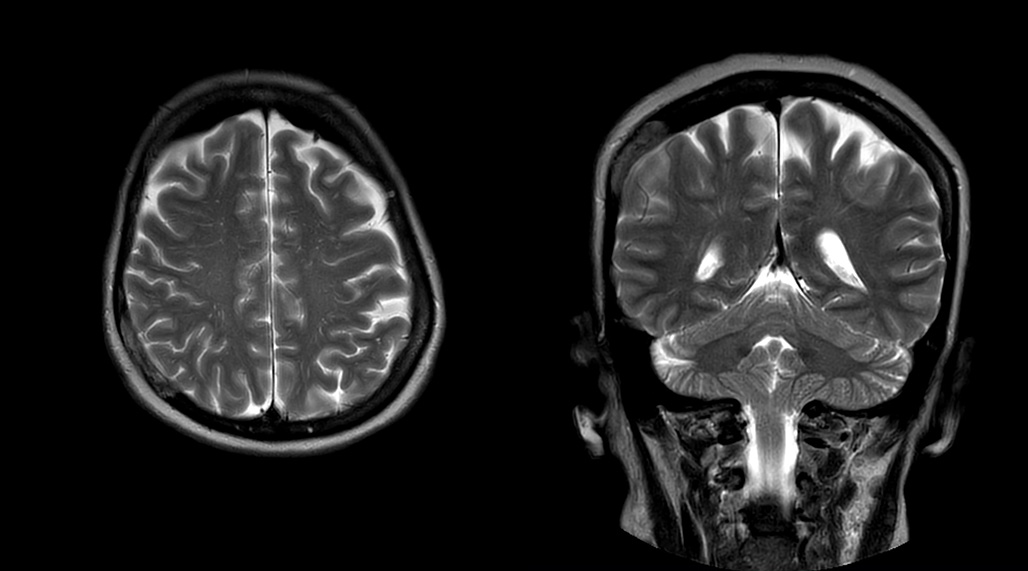

Patrick Duffy BS, RT (R) MR is Lead Technologist at DMG. “We are getting phenomenal image quality on all types of exams,” he says. “Our MSK is stellar, and so is our abdominal work. Ingenia excels at feet, hands and fingers. We do enterographies with great results. With the combination of the 3.0T magnet and the digital coils, we are able to scan prostates without an endorectal coil while still obtaining high quality results. This is a comforting experience for our male patients. We scan many obese patients, and the Ingenia does a tremendous job because of MultiTransmit, which reduces dielectric shading for more confident diagnosis. Our technologists really enjoy scanning on the Ingenia. We also have ordering physicians who specifically want their patients scanned on the Ingenia because of the results of our imaging.

“Obviously, the diagnostic capability is most important,” says Dr. Kaakaji. “Ingenia’s image quality is excellent and in follow-up studies, Ingenia provides good consistency between scans.

“Without using an endorectal coil we do our prostate MR at 0.5 mm resolution, following the European society of urology protocol [1]. For certain joints we use a virtual arthroscopy protocol with 1 mm pixel size and 2 mm slice thickness. Ingenia really excels in our neurography, brachial plexus and prostate scans. Our neurologists insist on using our 3.0T for those,” Dr. Kaakaji adds.

DMG recognizes MultiVane XD motion compensation is another Philips technique that contributes to image quality and scan efficiency. “We run MultiVane XD for motion-free imaging on almost all our T2-weighted brain scans, just to reduce any repeats we might get. We know our non-contrast brain scans are going to take 20 minutes almost every time,” Mr. Duffy says.

“Using MultiVane XD still allows us to turn on dS SENSE, which significantly cuts scan time compared to what we were doing before,” he adds. “We went from a 2.5 or 3-minute scan to a 1.5-minute scan with no loss in image quality. So, it not only reduces the motion, but also reduces scan time. That gives us a little bit of extra time to speak to our patients and explain the exam a little more.”